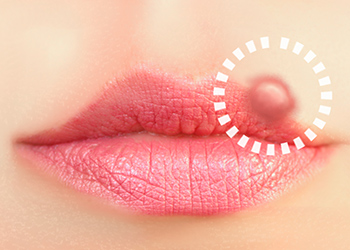

唇のしこりは病気?考えられる原因5つと治療法・予防法を解説!歯のアンテナ。

唇のできもの 白いブツブツやザラザラの原因は? 症状別に解説 医師監修- SillHa.com - 歯と口と身体の健康メディア -シルハドットコム- SillHa.com - 歯と口と身体の健康メディア -シルハドットコム。

唇のぶつぶつの3つの原因「自然治癒する?」「お薬は?」水疱・白いできものなどMedicalook メディカルック。

唇に白い斑点ができる原因は?受診目安や日常生活での注意点も解説! – ココシカ。